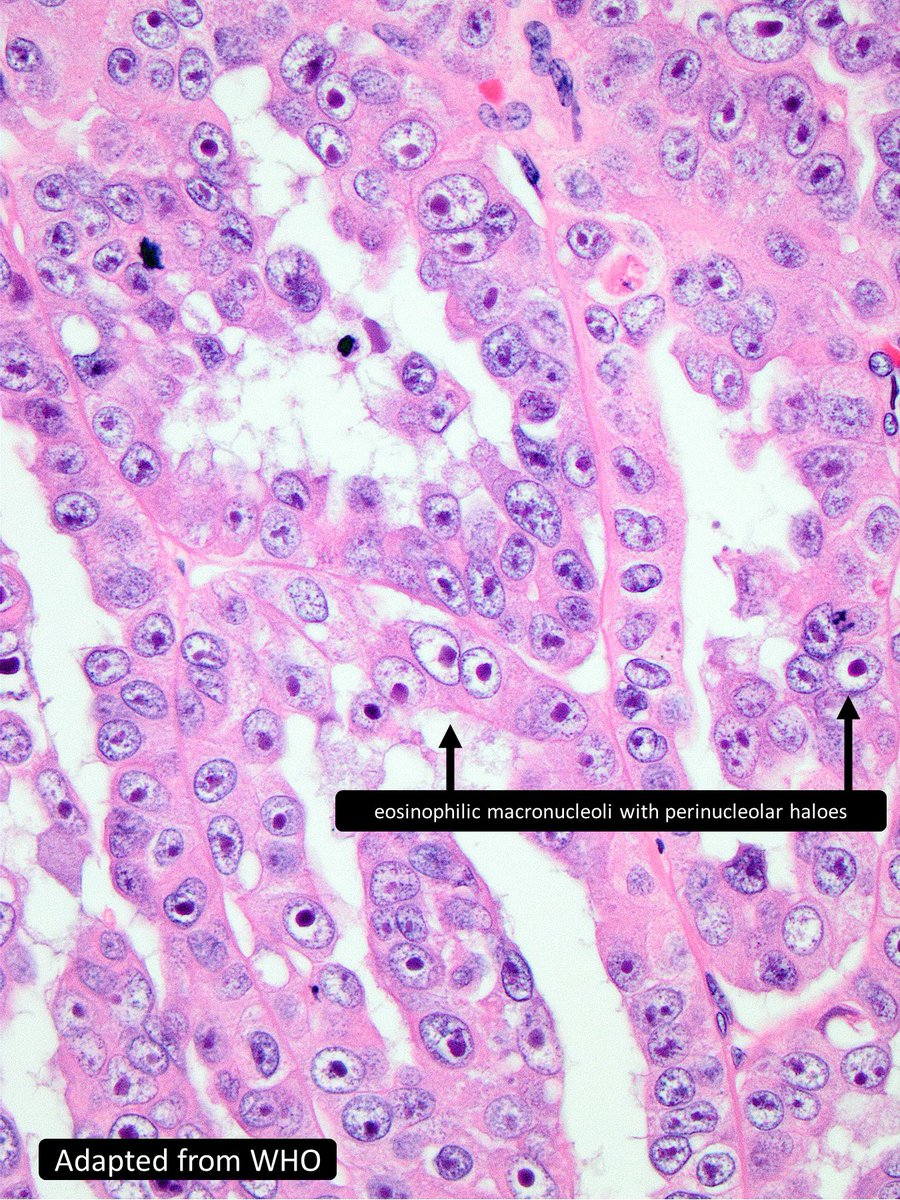

Hereditary Leiomyomatosis and Renal Cell Carcinoma - ERKNet/ERA Webinar ... youtu.be/Zypr2QNvQno?si… via @YouTube